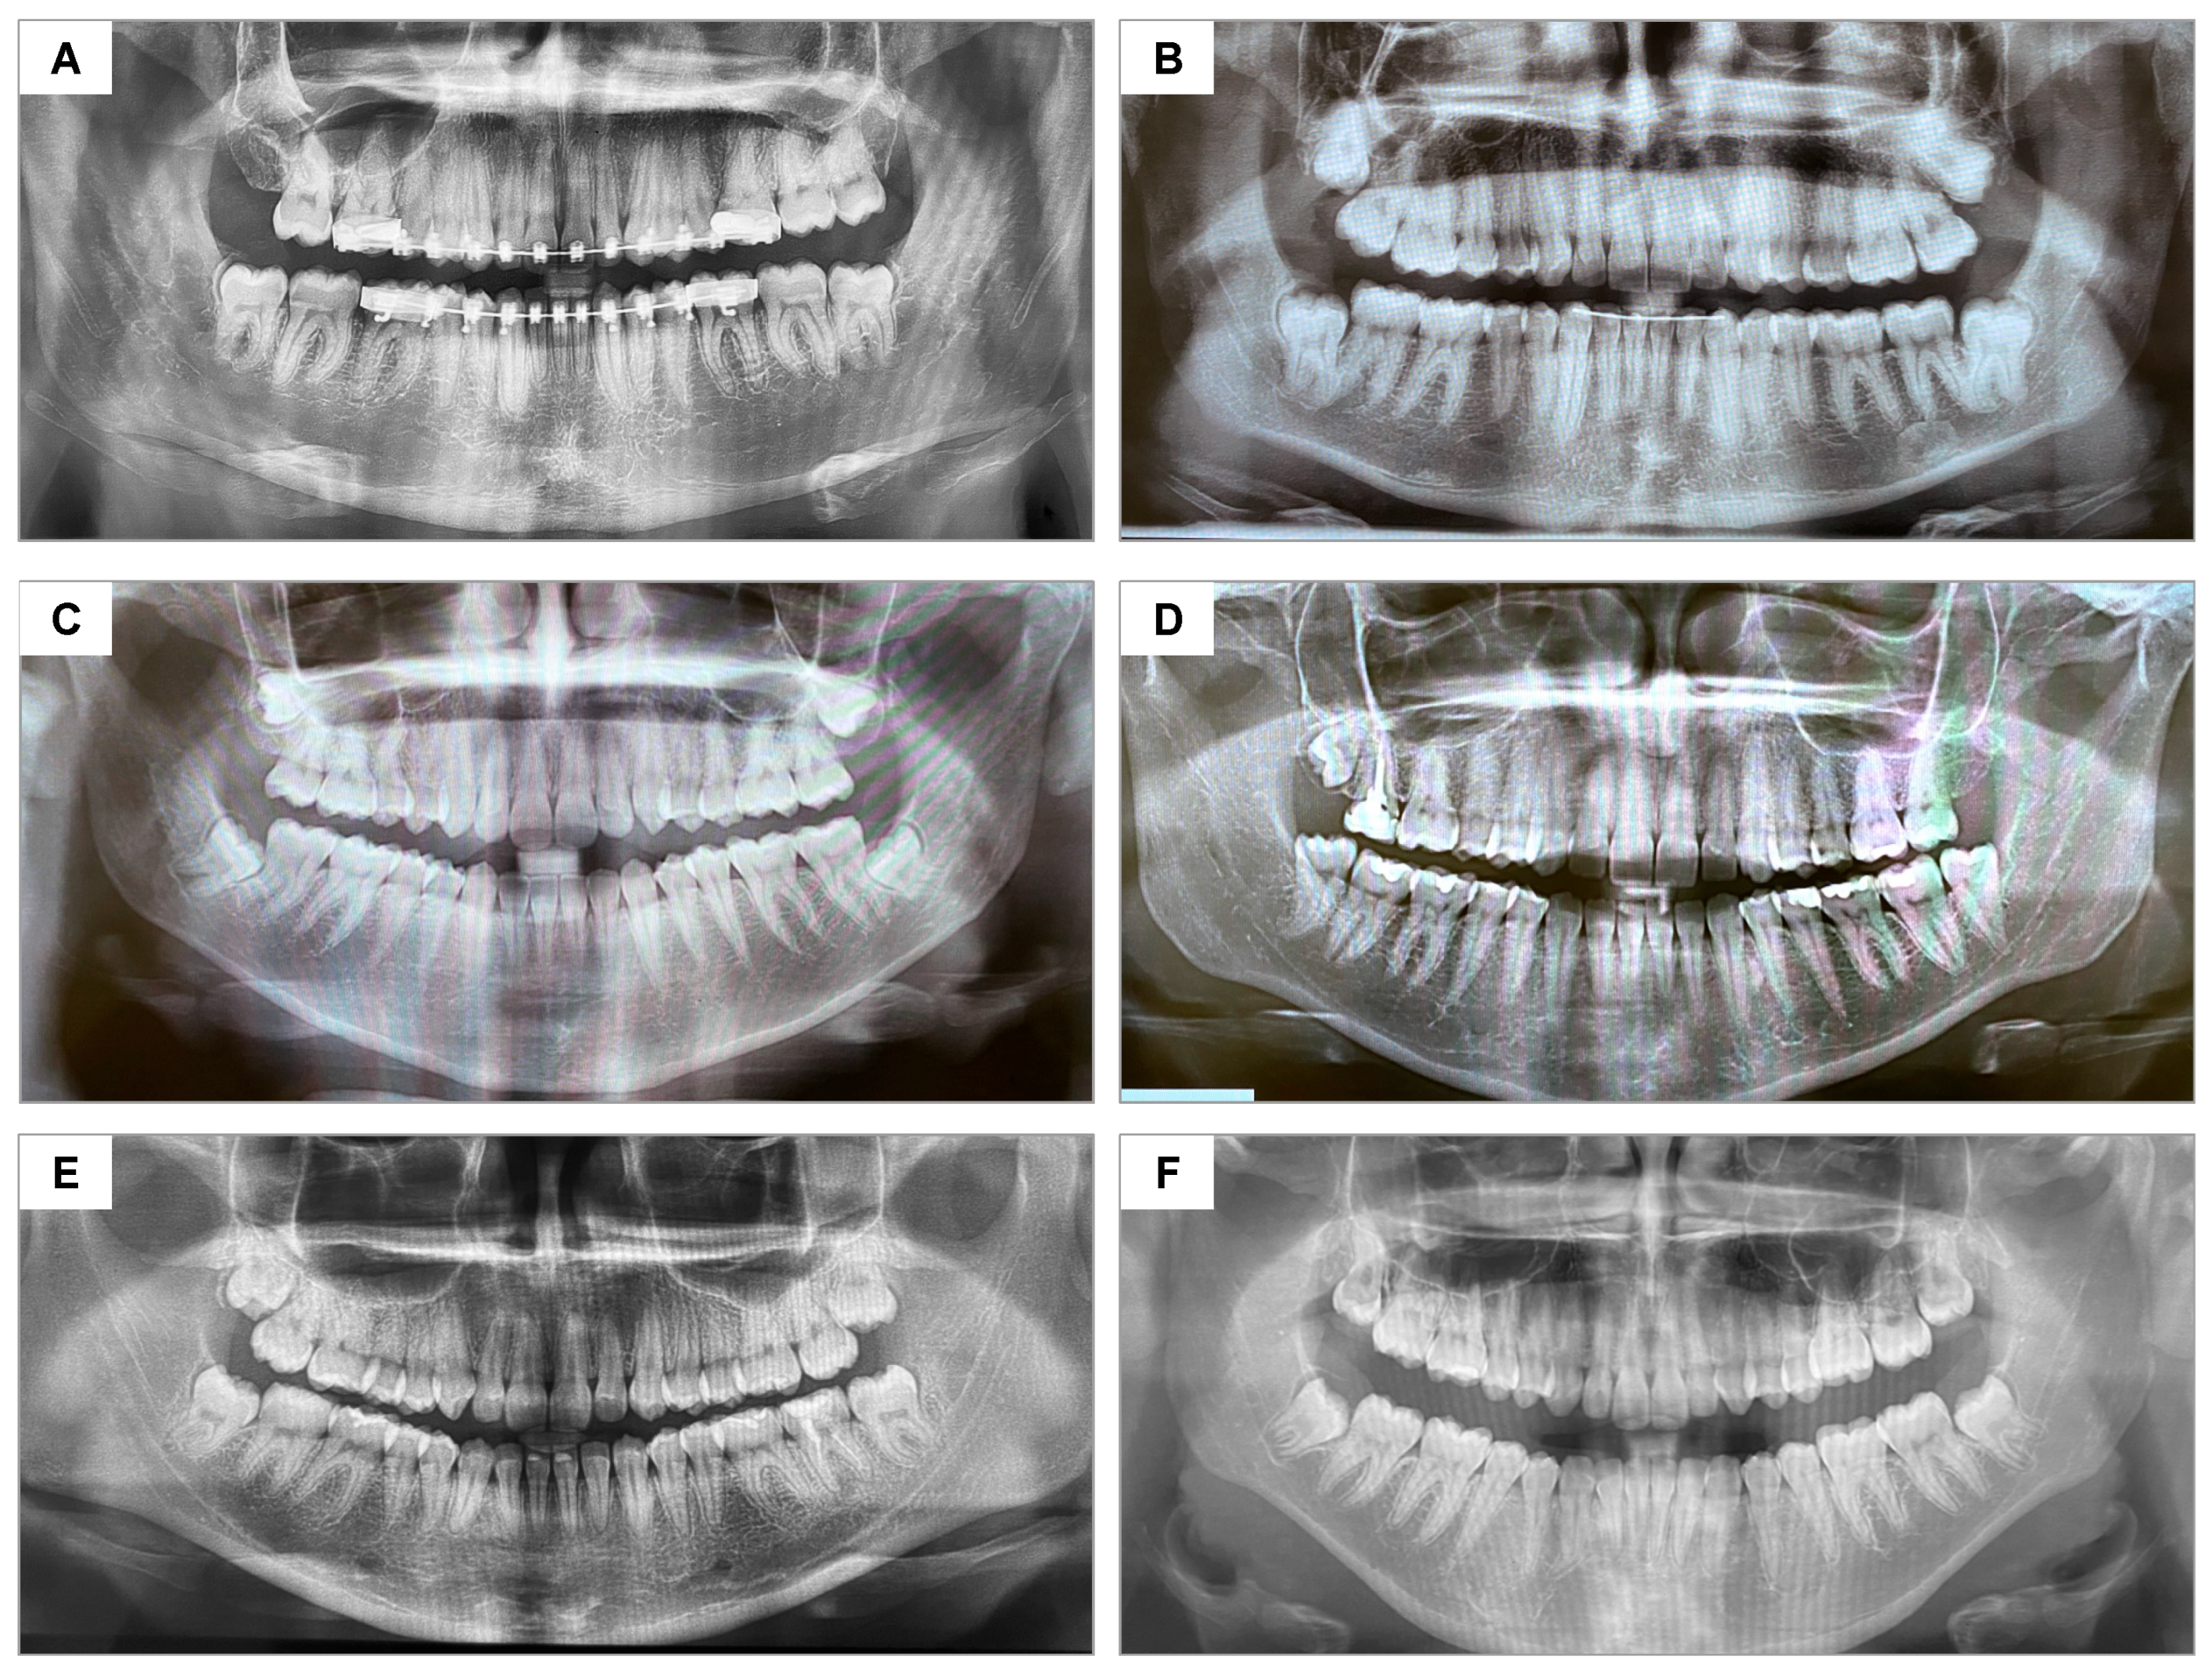

No dropout occurred, as shown in the CONSORT flowchart (Figure 5). No postoperative complications (e.g., infection, dry socket, or hemorrhage) were observed during evaluation periods. The control and test groups were considered homogeneous regarding the degree of difficulty of the extractions (Figure 6).

Figure 6. Panoramic radiographs representing the similarity in positioning and surgical difficulty of the lower third molars: (A) participant #18—A.G.S.J; (B) #7—M.P.M.B.; (C) #6—M.C.G.; (D) #4—J.A.A.L.; (E) #3—K.B.S.; (F) #11—B.V.R.